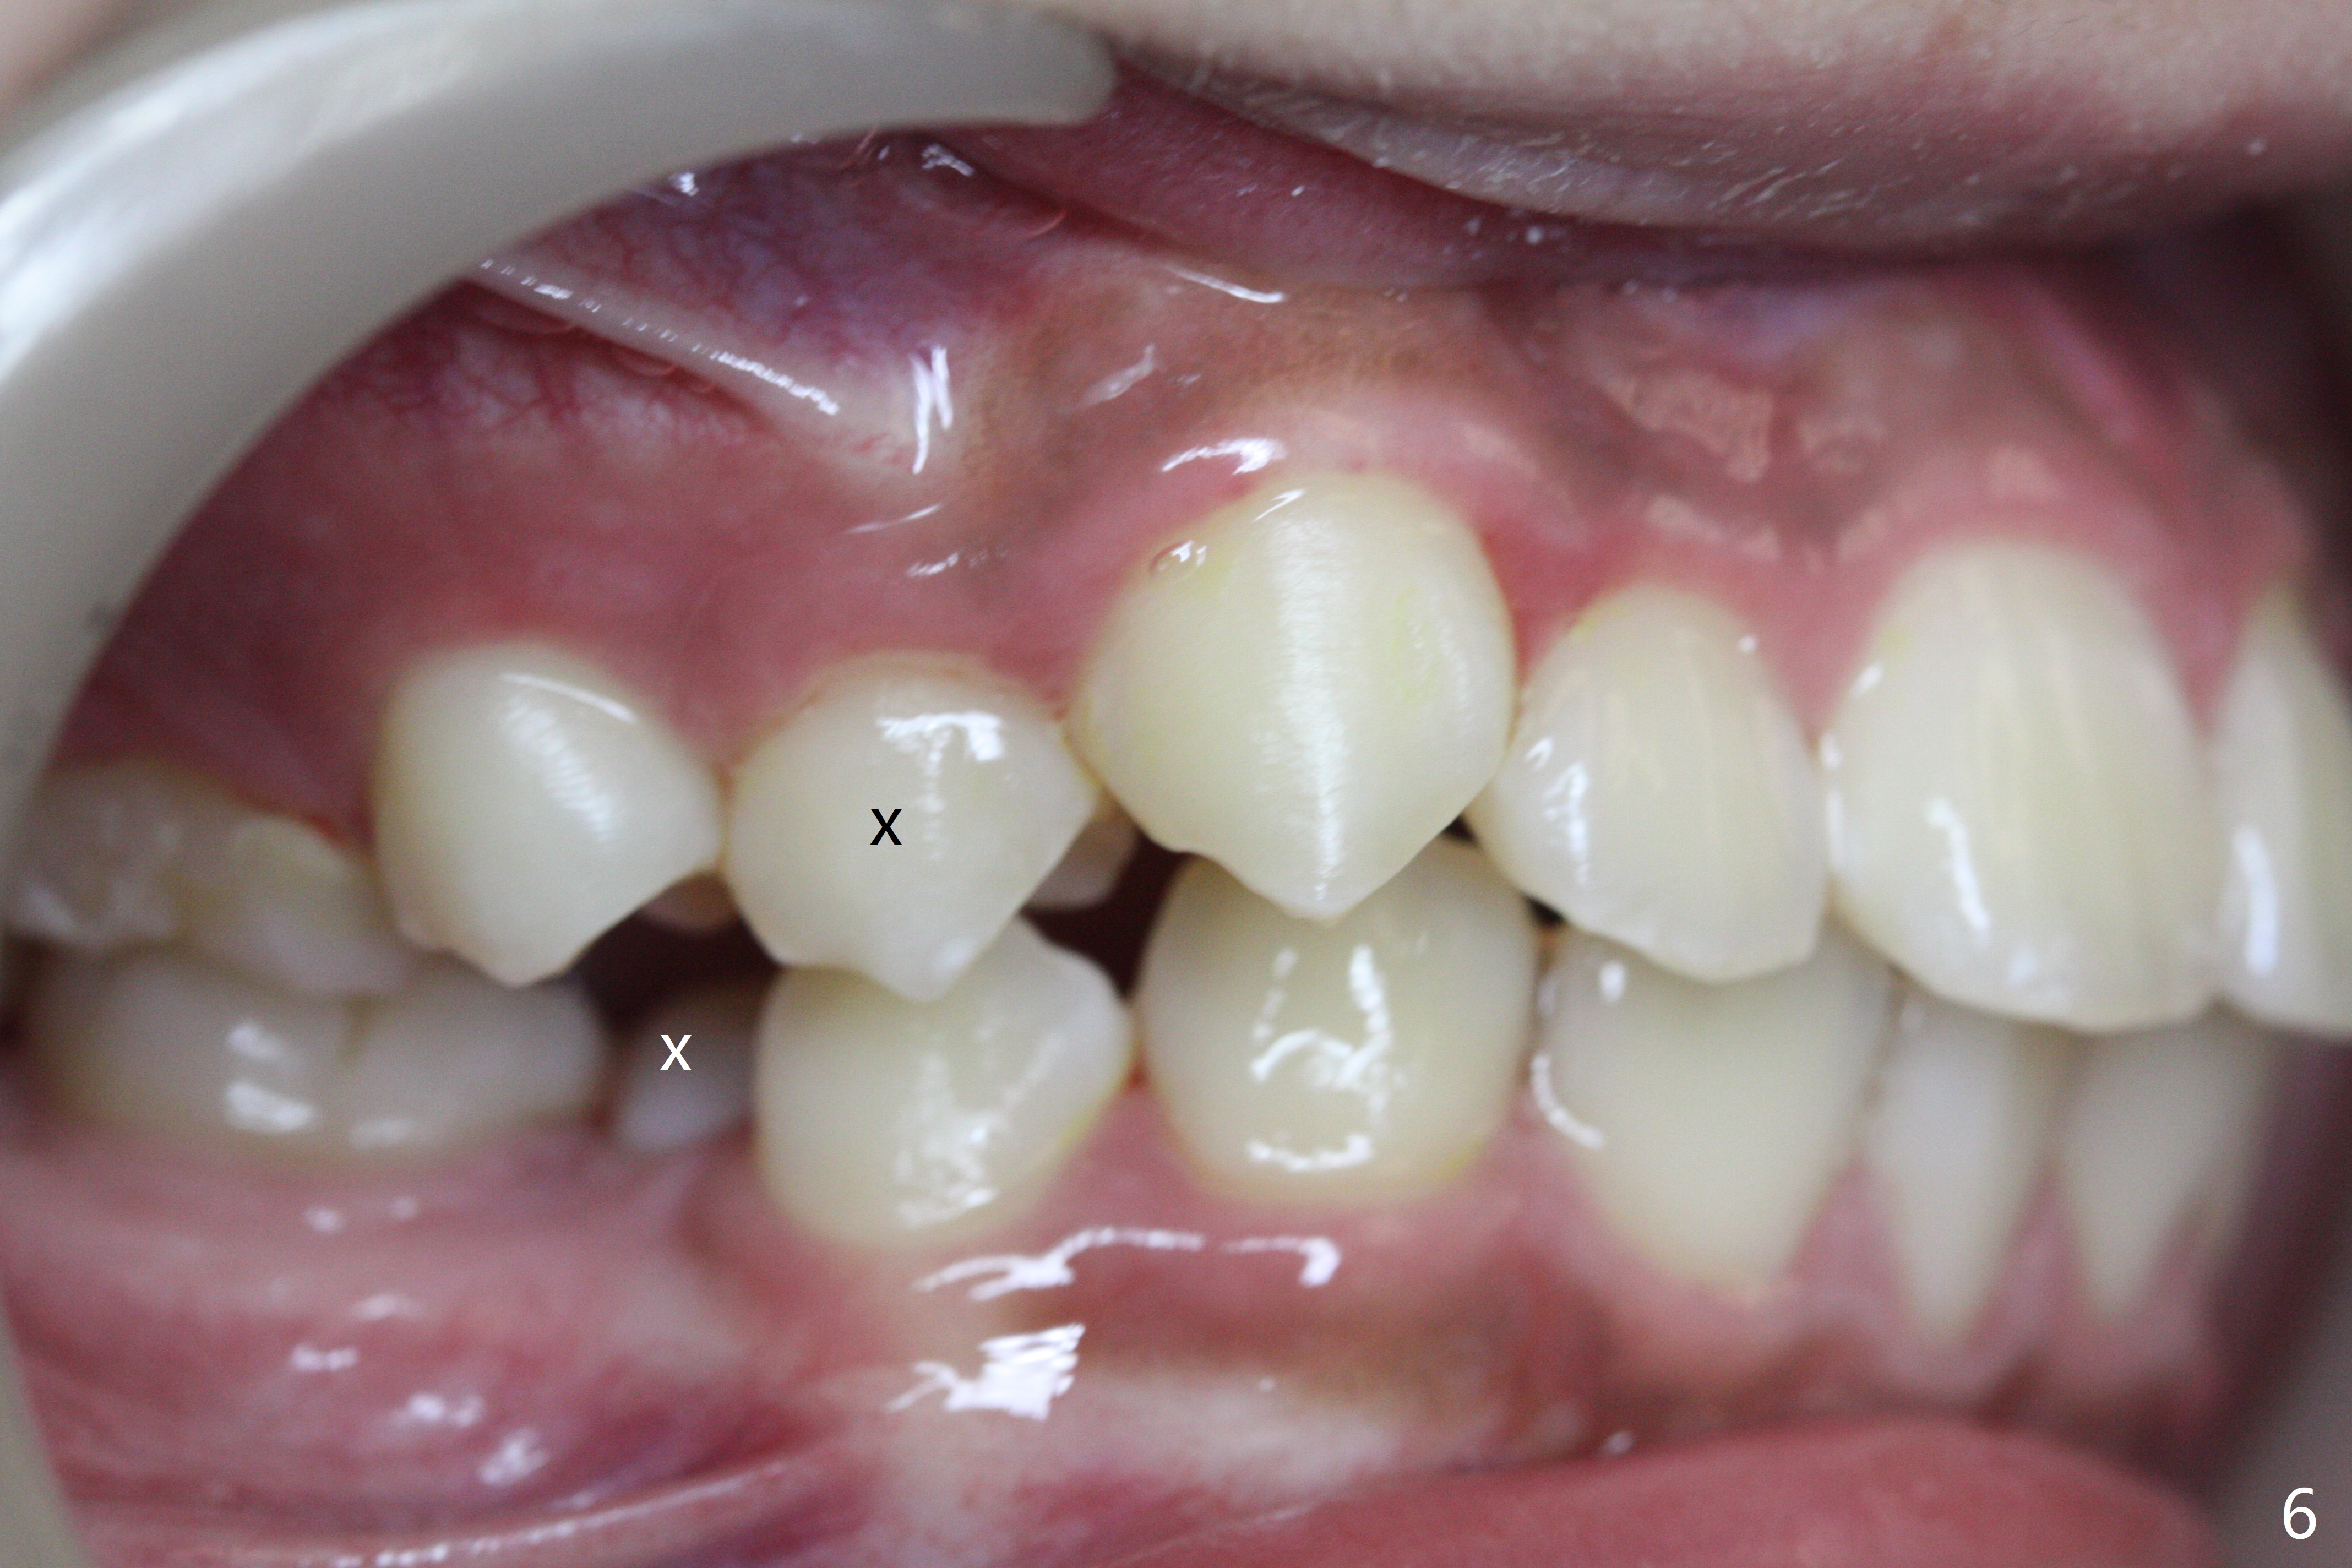

A 13-year-old man has protrusive lips (Fig.1,3,4) with upper midline deviation to the left (Fig.2).  Crowding is severe with LR5 severe lingual inclination (Fig.5,6,10).  To facilitate L6s' uprighting (Fig.10), LR5 and 3 of the 1st bicuspids will be extracted (Fig.6-8 x or *) and molar bands with lingual cleats will be used for the lower.  Cross arch molar retraction will be initiated immediately.  Open coil spring will be placed between UL1 and 3 with the 1st wires to correct the upper midline deviation and to gain the space for UL2.

The patient will return 2 months post extraction.  Shifting is expected to occur next to extraction sites (*) as indicated by arrows in Fig.9,11.  Take photos if it is the case.  Place bracket at UL2 if there is no space issue, but upside down (why?).  The most flexible wire is anticipated.  To establish Class I occlusion when wires are stiffer (18ss), LL5,6 will be mesialized as equally as LL3 distalized, while UL5,6 maintained basically in situ (Fig.11).  How to accomplish?